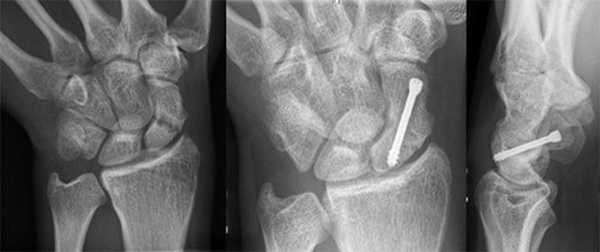

После этого пациенту необходимо пройти аппаратное исследование. При данном виде травмы достаточно пройти рентген, причем пациенту необходимо сделать два снимка, в двух проекциях. В некоторых медицинских учреждениях пациенту может быть предложено пройти магнитно-резонансную томографию, но необходимость в ней есть только при множественных травмах запястья, со смещением костей и костных осколков.

Если у человека подозревается перелом запястья руки его нужно обследовать. Большое значение приобретают жалобы и то, как человек получил травму. Немаловажное значение имеет осмотр врача, на его основании назначается рентгеновский снимок. Поскольку в области запястья много различных костей, рентгеновский снимок выполняется не в двух, а в трех проекциях (прямой, боковой и 3/4).

Поскольку часто повреждается ладьевидная кость, ее повреждение видно на снимке в виде линии. Когда перелома не видно на снимке сразу после травмы, накладывается гипс сроком на 3-5 дней. За этот период повреждение начинает срастаться и симптомы перелома руки запястья дополняются расширением линии перелома на снимке.

При возникновении сложностей в диагностике показано проведение компьютерной томографии (КТ). Методика позволяет показать врачу состояние костной ткани, особенно если дело касается ладьевидной кости. При подозрении на повреждение связок, хрящей или других мягкотканых структур показано проведение МРТ.

Основным показанием к оперативному вмешательству является перелом руки в запястье со смещением. Во время вмешательства анестезия общая, а суть операции состоит в фиксации отломков при помощи спицы или винта. Это приводит к плотному сдавлению отломков ладьевидной кости и надежной фиксации. Врачом может быть применен аппарат внешней фиксации. Процесс сращения занимает от одного до двух месяцев, восстанавливается активность лучезапястного сустава. Оперативное вмешательство при переломе остальных костей не проводится, только если есть значительное смещение.

В обязательном порядке выполняется рентгенография в 2-х проекциях. При необходимости врач может назначить компьютерную томографию. Ее выполняют в том случае, если перелом внутрисуставный, со смещением или было проведено хирургическое вмешательство для удаления осколков.

Если произошел перелом лучезапястного сустава со смещением, то необходимо на 10, 21 и 30 день делать рентген, чтобы убедиться, что после наложения повязки не произошло повторное смещение костей.